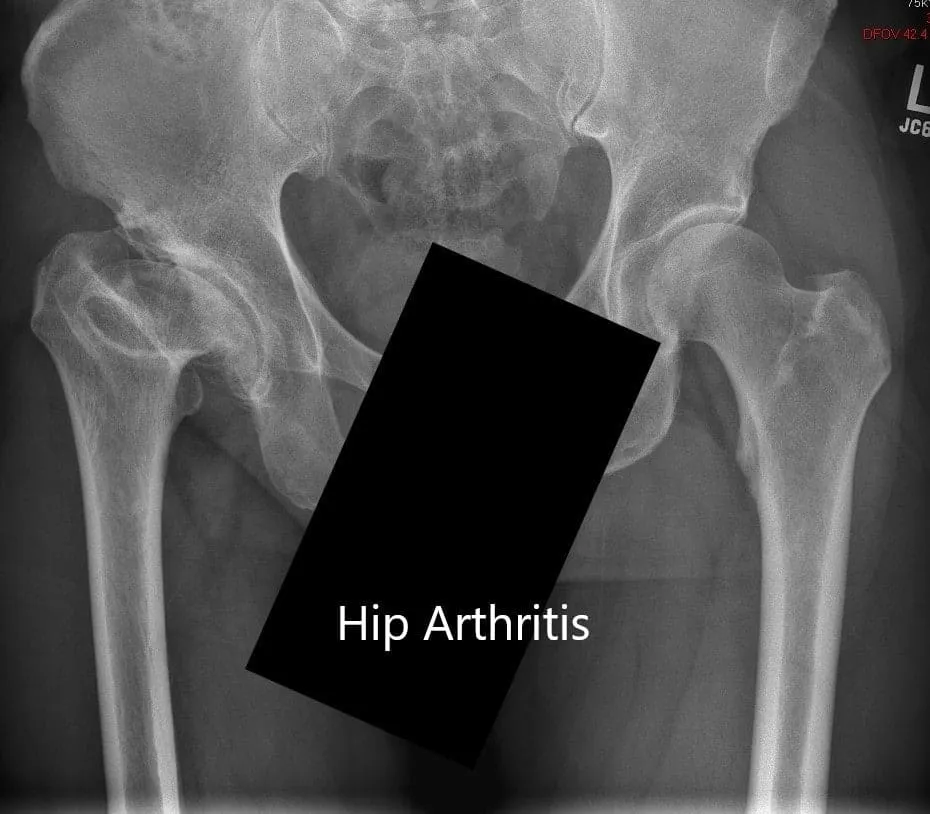

Preoperative X-ray showing the AP view of the pelvis with both hip joints

AP and lateral views of the right hip joint

Imaging revealed markedly deformed right femoral head and impacted the femoral neck. There were severe degenerative changes of the right hip.